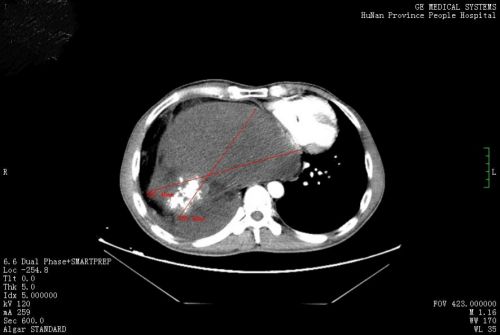

术前ct显示:包块挤压右肺。

胸部CT检查发现,其右侧胸、腹腔内有一个巨大包块压迫右肺,因此出现胸痛、胸闷等不适。进一步检查考虑,巨大包块来源于后纵膈,畸胎瘤的可能性大。心胸外科医师会诊后,将他收入心胸外科病房准备手术治疗。

“这个畸胎瘤长在右侧胸腔,体积巨大,压迫右肺、心脏等脏器,手术难度和风险极大”,心胸外科周文武主任医师团队对患者病情进行认真讨论、评估,并做好充足准备后,于83日为其施行“右侧胸腔占位切除+左心房成形术”。